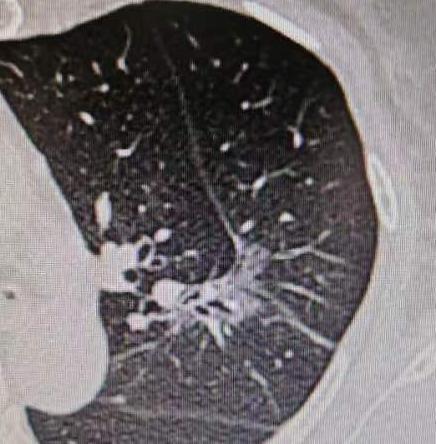

为了一个6mm的小结节,切掉一大块肺?如果是这样的手术,我坚决不做!今年38岁的

2025-11-25

乔贵

标签:

医生

肺结节

肿瘤

体检